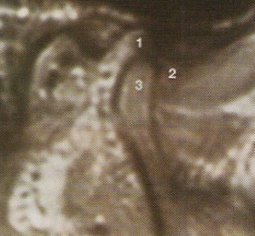

De ésto nos van a informar en radiología al realizar una RMN de ATMs. Esta prueba se muestra especialmente útil y superior a los restantes métodos de diagnóstico por imagen, en el estudio de la posición del disco articular y de sus anomalías de posición (desplazamientos discales) y estructurales. En condiciones normales, cuando se explora la ATM en boca cerrada y en cortes sagitales, el disco aparece como una cinta grisácea oscura situado entre el cóndilo y la eminencia temporal; el extremo anterior (banda anterior) se halla en la posición horaria de las 9 mirando a la cima de la eminencia, y el extremo posterior (banda posterior), más grueso, en la posición de las 12 de la cabeza condílea.

La banda posterior en relación con la cabeza condílea es el punto de referencia para apreciar la posición y desplazamiento del disco; así, se considera que hay desplazamiento discal anterior cuando, con la boca cerrada, el disco está por delante de la posición horaria de las 12 con respecto a la cabeza condílea.

Se deben realizar 3 cortes sagitales angulados (lateral, central y medial), para poder hacer un diagnóstico correcto de las alteraciones de las ATMs.